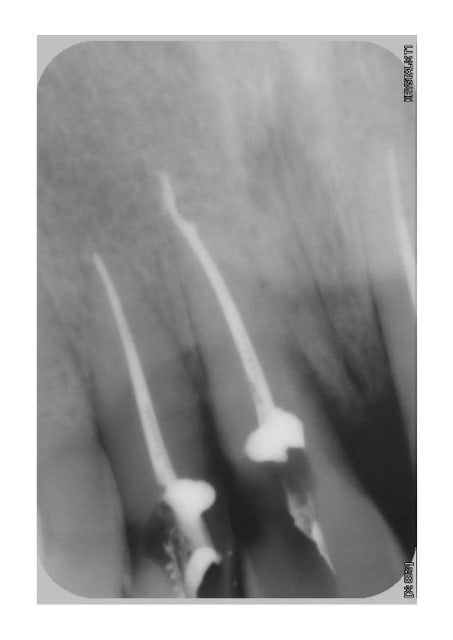

dévitalisation retraitement de 22/21/11/12 et 26 remplacement des amalgames par du composite et tout le reste dents vivantes.

le patient ne fume plus depuis 21 jours sur les dernières photos, mais je ne sais pas si mon plan de traitement suffira à lui redonner une gencive correcte.